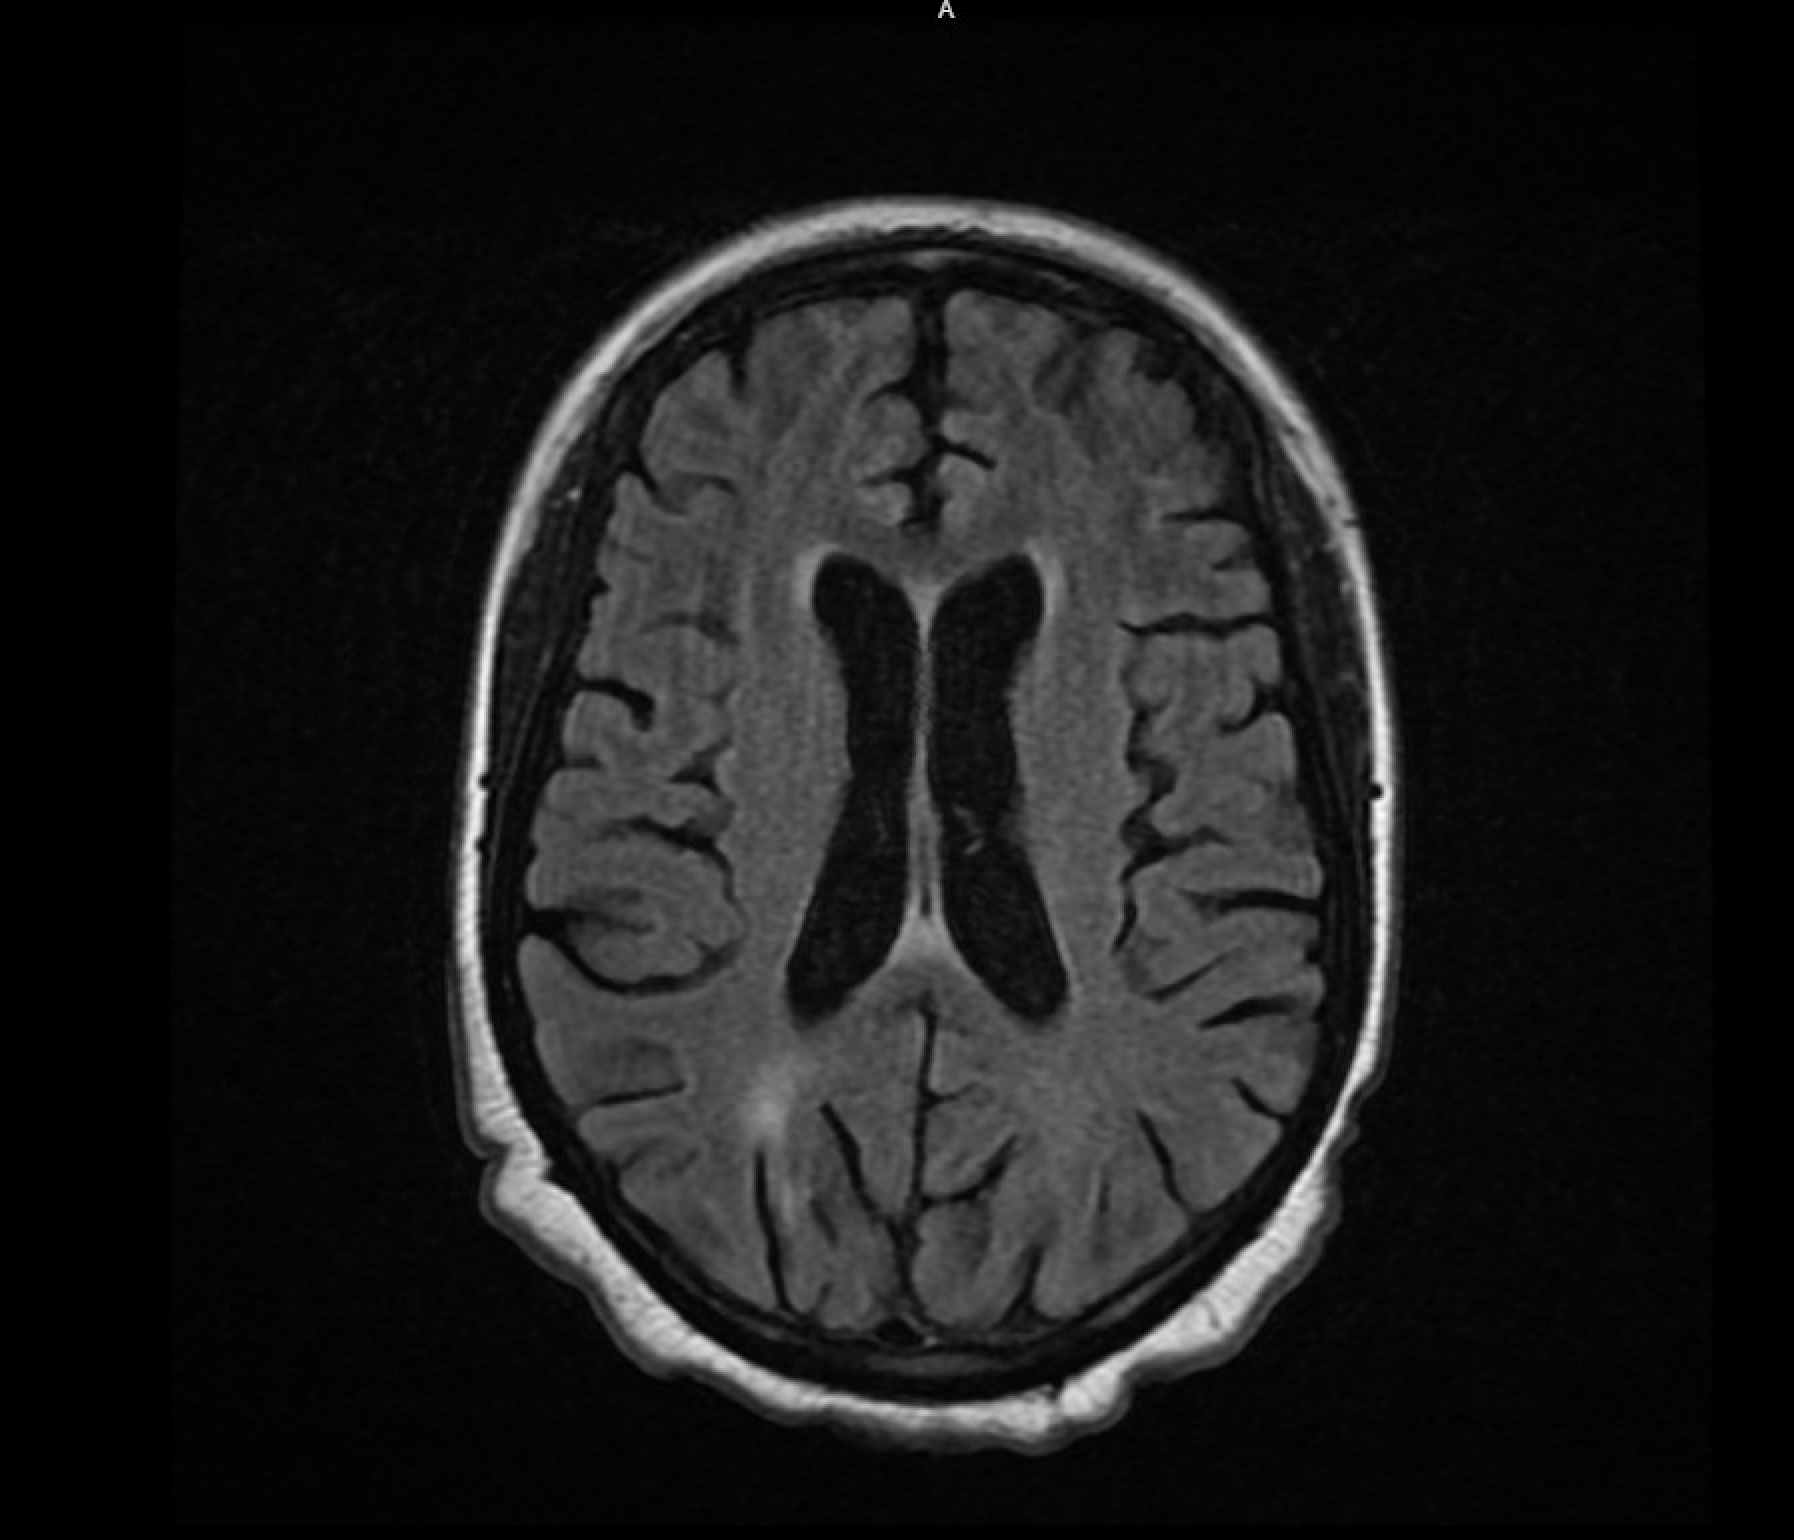

Case Presentation: A 27 year old woman with systemic lupus erythematosus (SLE) and history of a single seizure episode presented with acute altered mental status. The patient was initially disoriented and nonverbal, able to open eyes but unable to track, intermittently responding to commands, and later deteriorating, becoming obtunded and eventually comatose. Her NIH Stroke scale was 2 and no focal deficits were noted during the hospitalization. MRI findings revealed mild-to-moderate brain atrophy with patchy periventricular and subcortical hyperintensities, suggesting an inflammatory process. After ruling out meningoencephalitis with a lumbar puncture, she was diagnosed with Neuropsychiatric SLE (NPSLE), later complicated by multiple unprovoked seizure-like episodes. Three 24-hour video electroencephalograms (vEEGs) were negative for epileptic activity despite the presence of postictal states and tongue lacerations. Her treatment for lupus cerebritis led to improvements in mental status and neurological symptoms, although seizure-like activities persisted. Despite repeated negative EEGs, the patient was started on Levetiracetam 500 mg alongside 1mg Lorazepam as needed. Notably, the patient retained memory of one episode, and experienced two panic attacks suggesting concomitant psychogenic non-epileptic seizures (PNES) and anxiety. These PNES events occurred after administration of Levetiracetam, supporting the possibility of a dual diagnosis.